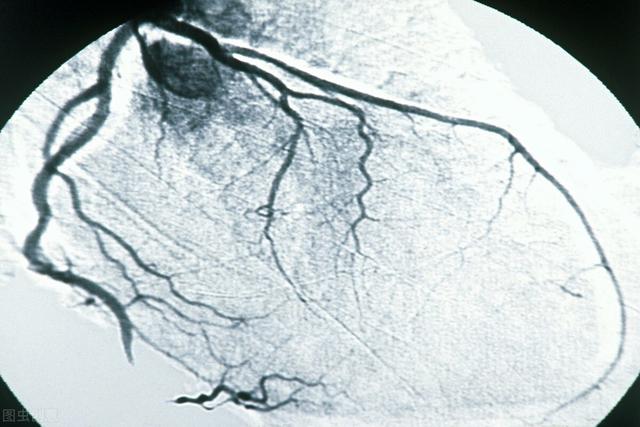

いよいよ心臓血管検査の王様についてお話ししましょう。冠動脈造影は私よりずっと古く,1959年にアメリカのクリーブランド・メディカル・センターのSones博士が最初の冠動脈造影を完成させてから,56年近い歴史がある。開始以来、冠動脈造影はその直感的で客観的な特徴から、冠動脈疾患のゴールドスタンダードとなっています。

冠動脈疾患の診断におけるゴールドインデックスの意義は、イエスかノーかという皇帝の遺言のようなものである。冠動脈についてどのような検査が行われたかにかかわらず、冠動脈造影が行われた以上、すべては冠動脈造影の結果に左右される。冠動脈造影検査とは、大腿動脈または橈骨動脈からボールペンの芯のような太いカテーテルを挿入し、冠動脈の開口部に入れ、造影剤を注入して画像を現像する方法で、造影剤下で冠動脈血管の配列、数、変形を観察し、冠動脈病変の有無、重症度、範囲を評価し、冠動脈の攣縮、側枝循環の有無など冠動脈の機能的変化を評価し、同時に冠動脈の左側も考慮して、冠動脈の機能的変化を評価することです。冠動脈の攣縮や側枝循環を含む冠動脈の機能的変化を評価し、同時に左心機能の評価も考慮することができる。この検査は基本的に電気生理学的検査を除くすべての心臓関連検査を網羅していると言える。

2、冠状動脈造影検査:これは侵襲的な検査で、動脈穿刺を通して、カテーテルを冠状動脈の開口部に入れ、造影剤を注入し、X線の下で血管内の充満状況と血流速度を観察します。このような検査は直接血管内の状況を見ることができるので、冠状動脈性心臓病の診断の黄金指標ですが、欠点はこのような検査は侵襲的な検査であるということです;

6.冠動脈造影(経皮経動脈的冠動脈造影法)手順動脈穿刺(手首の橈骨動脈または太ももの付け根の大腿動脈)で冠動脈の開口部にカテーテルを送り、ヨード造影剤を注入して冠動脈の形態と血流を観察し、一般に50%以上の狭窄があれば冠動脈疾患と診断する。この方法は現在、冠動脈疾患を診断するための "ゴールド・スタンダード "である。その利点は、正確であること(もちろん、投影の角度や医師の経験、血管の変形などにより、不正確な場合もある)、問題が発見された直後にバルーン拡張術やステント留置術(その他の手技も含む)により冠動脈を開いて血液供給を改善し、問題の発見と治療を同時に行えることである。この方法は低侵襲で、確かな技術と優れた安全性を備えた手技である。しかし、手技である以上、傷害やリスク、造影剤と同じ問題がある。

- 冠動脈造影は高度な配管工事である。冠動脈造影の原理は冠動脈CTAと似ているが、冠動脈造影は侵襲的な検査で、手や大腿の動脈から心臓の冠動脈まで管を送り、冠動脈に直接造影剤を注入し、冠動脈の形態をフィルムカメラで見る(DSA)。この検査は冠動脈疾患の診断のゴールドスタンダードであり、冠動脈の主幹や太い枝だけでなく、細い枝の一部も見ることができる。冠動脈疾患の診断手段としてだけでなく、冠動脈インターベンション治療と呼ばれる、このカテーテルを通してバルーンやステントなどを送り込んで治療する手段としても使用できるため、何よりも高度な配管工と言われている。

4.冠動脈造影:冠動脈疾患診断の "ゴールドスタンダード "である。冠動脈の狭窄の有無、狭窄の程度、範囲、位置などを明らかにし、さらに治療の指針を得ることができる。同時に、左心室造影は心臓の機能を評価することができる。